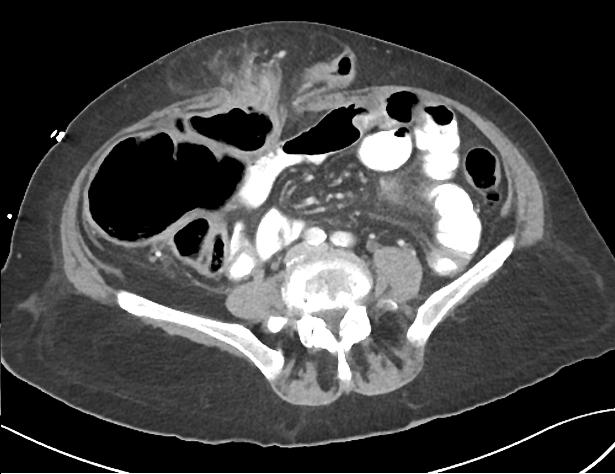

Occlusion du colon : Volvulus

deux jambage de l'anse sigmoide ( etoile ) . |

Image TDM en coupe coronale

enserrant le meso sigmoide . |